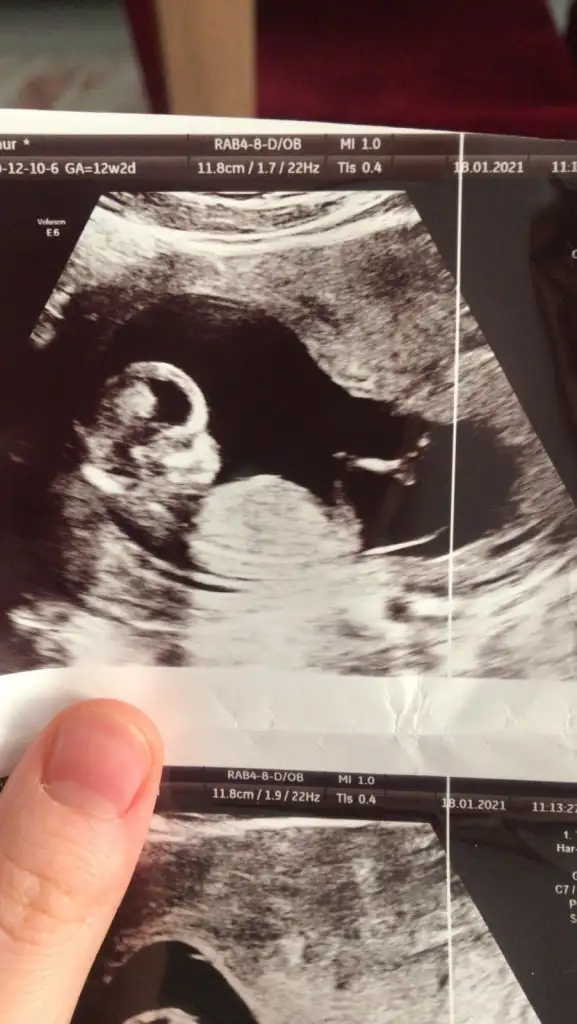

Buradaki hanımların nub teorisine göre kız gibiEki Görüntüle 2764421 Eki Görüntüle 2764422 Eki Görüntüle 2764423 Tahminde bulunur musunuz arkadaşlar

erkek gibi amaHanımlar sizce benim kuzumun cinsiyeti ne fikirlerinizi alabilir miyim lütfen??